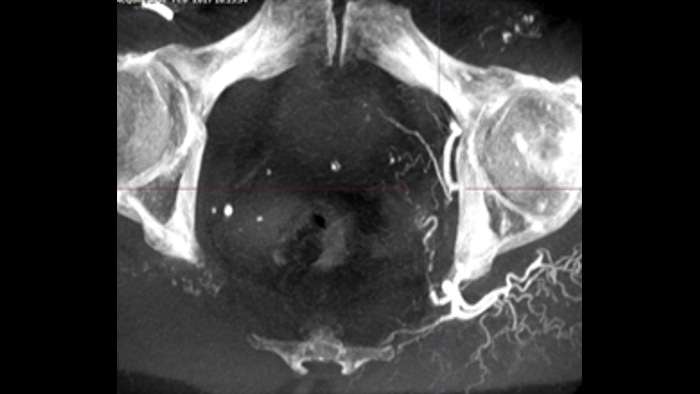

SmartCT Soft Tissue bietet eine Cone-Beam-CT-Erfassungstechnik (CBCT), die durch Schritt-für-Schritt-Anleitungen, erweiterte 3D-Darstellungs- und Messwerkzeuge, die alle auf dem Touchscreen-Modul am Tisch zugänglich sind, ergänzt wird. Damit Ihre CBCT-Bilder auf Anhieb gelingen und Ihr Arbeitsablauf effizient gelingt, werden Sie durch die wichtigsten Schritte geführt.

SmartCT Vaso bietet 3D-Bildgebung mit hoher Auflösung, die wichtige zerebrovaskuläre Strukturen darstellt und so die räumliche Beurteilung von Gefäßen auf hohem Niveau unterstützt.